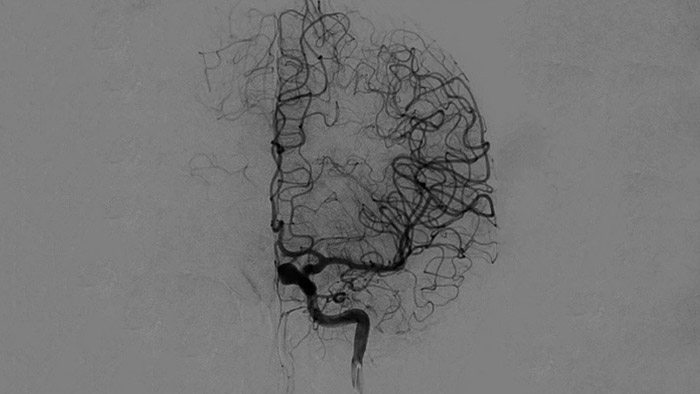

Четкие изображения при помощи 2D DSA с использованием технологии ClarityIQ

2D DSA с использованием технологии ClarityIQ

Технология ClarityIQ применяет опцию автоматической компенсации артефактов движения во время проведения DSA в режиме реального времени, чтобы создавать четкие изображения сосудов. Это способствует принятию верных решений во время операций по лечению инсульта.

Визуализация DSA

Высококачественная визуализация в режиме DSA позволяет оценить, был ли тромб полностью удален и произошло ли растворение сгустков крови в головном мозге. Врачам предоставляется возможность проверить восстановление кровотока в области ишемической полутени, а также наличие кровотечений в периоперационный период.